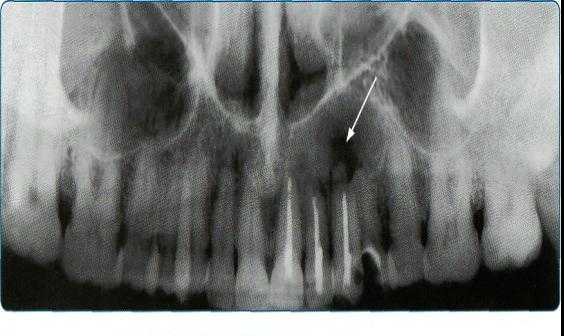

3. Переломы корня

Достаточно тщательно изучена польза и важность КЛКТ в процессе постановки диагноза и ведения зубоальвеолярной травмы, особенно переломах корня, люксации, смещения и переломе альвеолярного отростка.

КЛКТ найдено применение конкретно при диагностике перелома корня зубов.

(Фото 7,8) Высокая важность КЛКТ в определении вертикальных и горизонтальных переломов корня были также описаны в литературе. Элиминация наложения анатомических структур позволяет клиницисту четко анализировать перелом. Вдобавок, 3D реконструкция может быть осуществлена как зубочелюстной системы, так и альвеолярной кости.

Фото 7: Перелом корня в эндодонтически леченом верхнем правом втором моляре

А: ОПГ, показывающая ранее леченые каналы верхнего правого первого моляра

B: Аксиальное изображение, демонстрирующее линию перелома по небному корню

С: Секционный снимок, показывающий косую линию перелома небного корня

Фото 8: горизонтальный перелом правого верхнего центрального моляра

А: 3D изображение, демонстрирующее линию перелома у соединения средней и апикальной трети корня

B: Аксиальный снимок, показывающий горизонтальную линию перелома в передней части верхнего правого центрального резца

С: Косая линия отлома, распространяющаяся от мезиального каря центрального резца на секционном снимке.